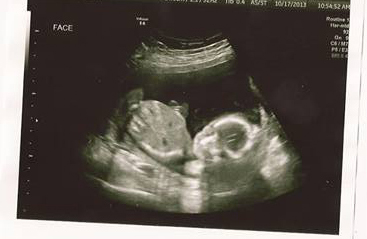

It's a healthy baby boy! His name is going to be Tristan Nicholas. Tristan's measurements are right where they should be. Everything with the baby looks great! The only concern the doctor has is they found venous lakes. They want to take a closer look at it so I've been referred to a place that has better U/S for high risk pregnancies. They want to keep an eye on it due to past pregnancy complications. Hopefully we'll get some good news when the U/S is done. We don't have a date for that yet, but the doctor said to expect a call for a date and time within the next couple days.